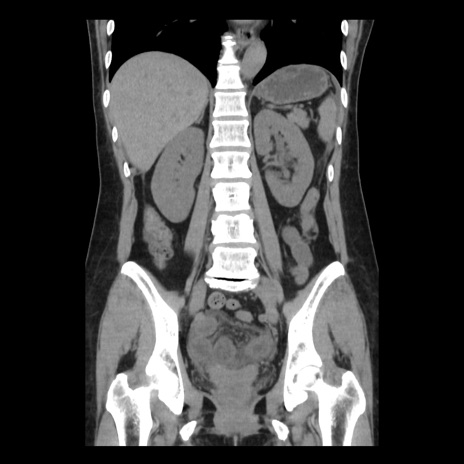

症例10(冠状断像)

【症例】 50歳代女性

【主訴】 腹痛

【現病歴】前日生レバーを食べた。今朝に排便あり。 昼前に突然発症の腹痛を生じ、当院救急外来を受診した。

【既往歴】 子宮筋腫にてで子宮全摘後

【身体所見】 意識清明、腹部:平坦、軟、下腹部やや左を中心に圧痛・反跳痛あり、筋性防御あり

【データ】WBC 7800、CRP 0.07